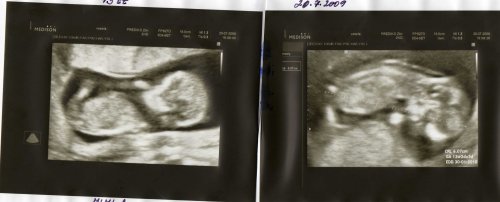

20.7. Prediko Zlín, screeining v 1.trimestru- vše OK,miminka s sebou mrskala jak splašená 🙂, no hold celý tatínek.....

10.9. 2009- 2. screening Prediko Zlín -oprava 11.9.-jsem popleta- vše ok- čekáme 2 chlapečky Bořka a Bruna....za 3 tt kontrola v Prediku- oba chlapečci jsou zdraví a šikovní.......